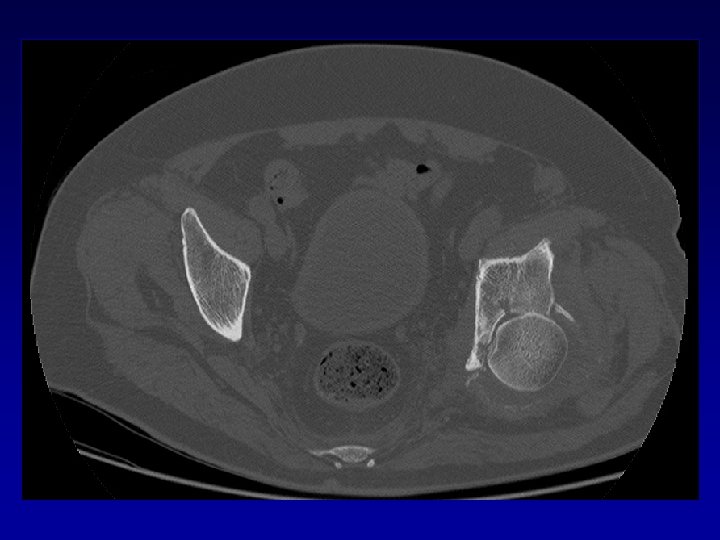

Ostéome Problème majeur - Scanner • Difficultés chirurgicales • Risque neurologique • Récidive

Déformation du cotyle • Ascensionné • Perte de substance osseuse scanner • Pseudarthrose •

Déformation du cotyle • Ascensionné • Perte de substance osseuse scanner • Pseudarthrose • Perte du positionnement exact (idem LCH) • Doit être reconstruit et recentré